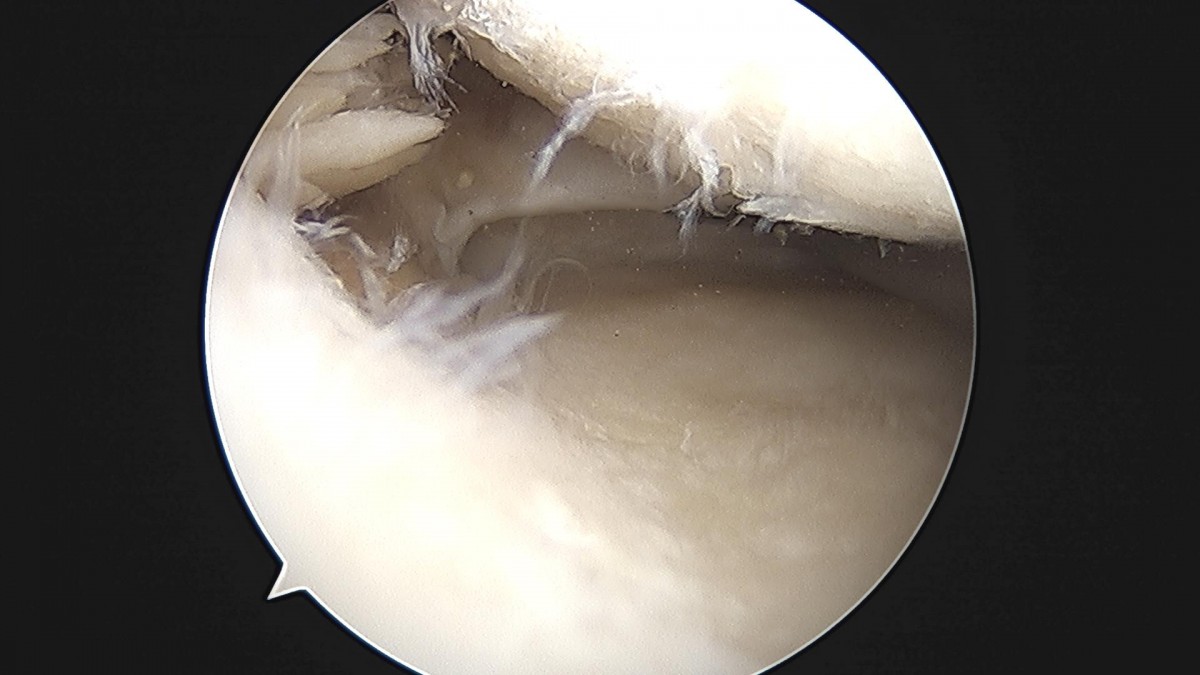

배우한 원장님 무릎 반월상 연골판 절제술 장인O 환자

8b0c7da4bf0a0c139df98fc62b3e688e_1702369141_0572.jpg

8b0c7da4bf0a0c139df98fc62b3e688e_1702369141_416.jpg

8b0c7da4bf0a0c139df98fc62b3e688e_1702369141_769.jpg

8b0c7da4bf0a0c139df98fc62b3e688e_1702369142_0792.jpg

8b0c7da4bf0a0c139df98fc62b3e688e_1702369142_3897.jpg

8b0c7da4bf0a0c139df98fc62b3e688e_1702369142_7482.jpg

8b0c7da4bf0a0c139df98fc62b3e688e_1702369143_046.jpg

8b0c7da4bf0a0c139df98fc62b3e688e_1702369143_354.jpg

8b0c7da4bf0a0c139df98fc62b3e688e_1702369143_701.jpg

8b0c7da4bf0a0c139df98fc62b3e688e_1702369144_0197.jpg